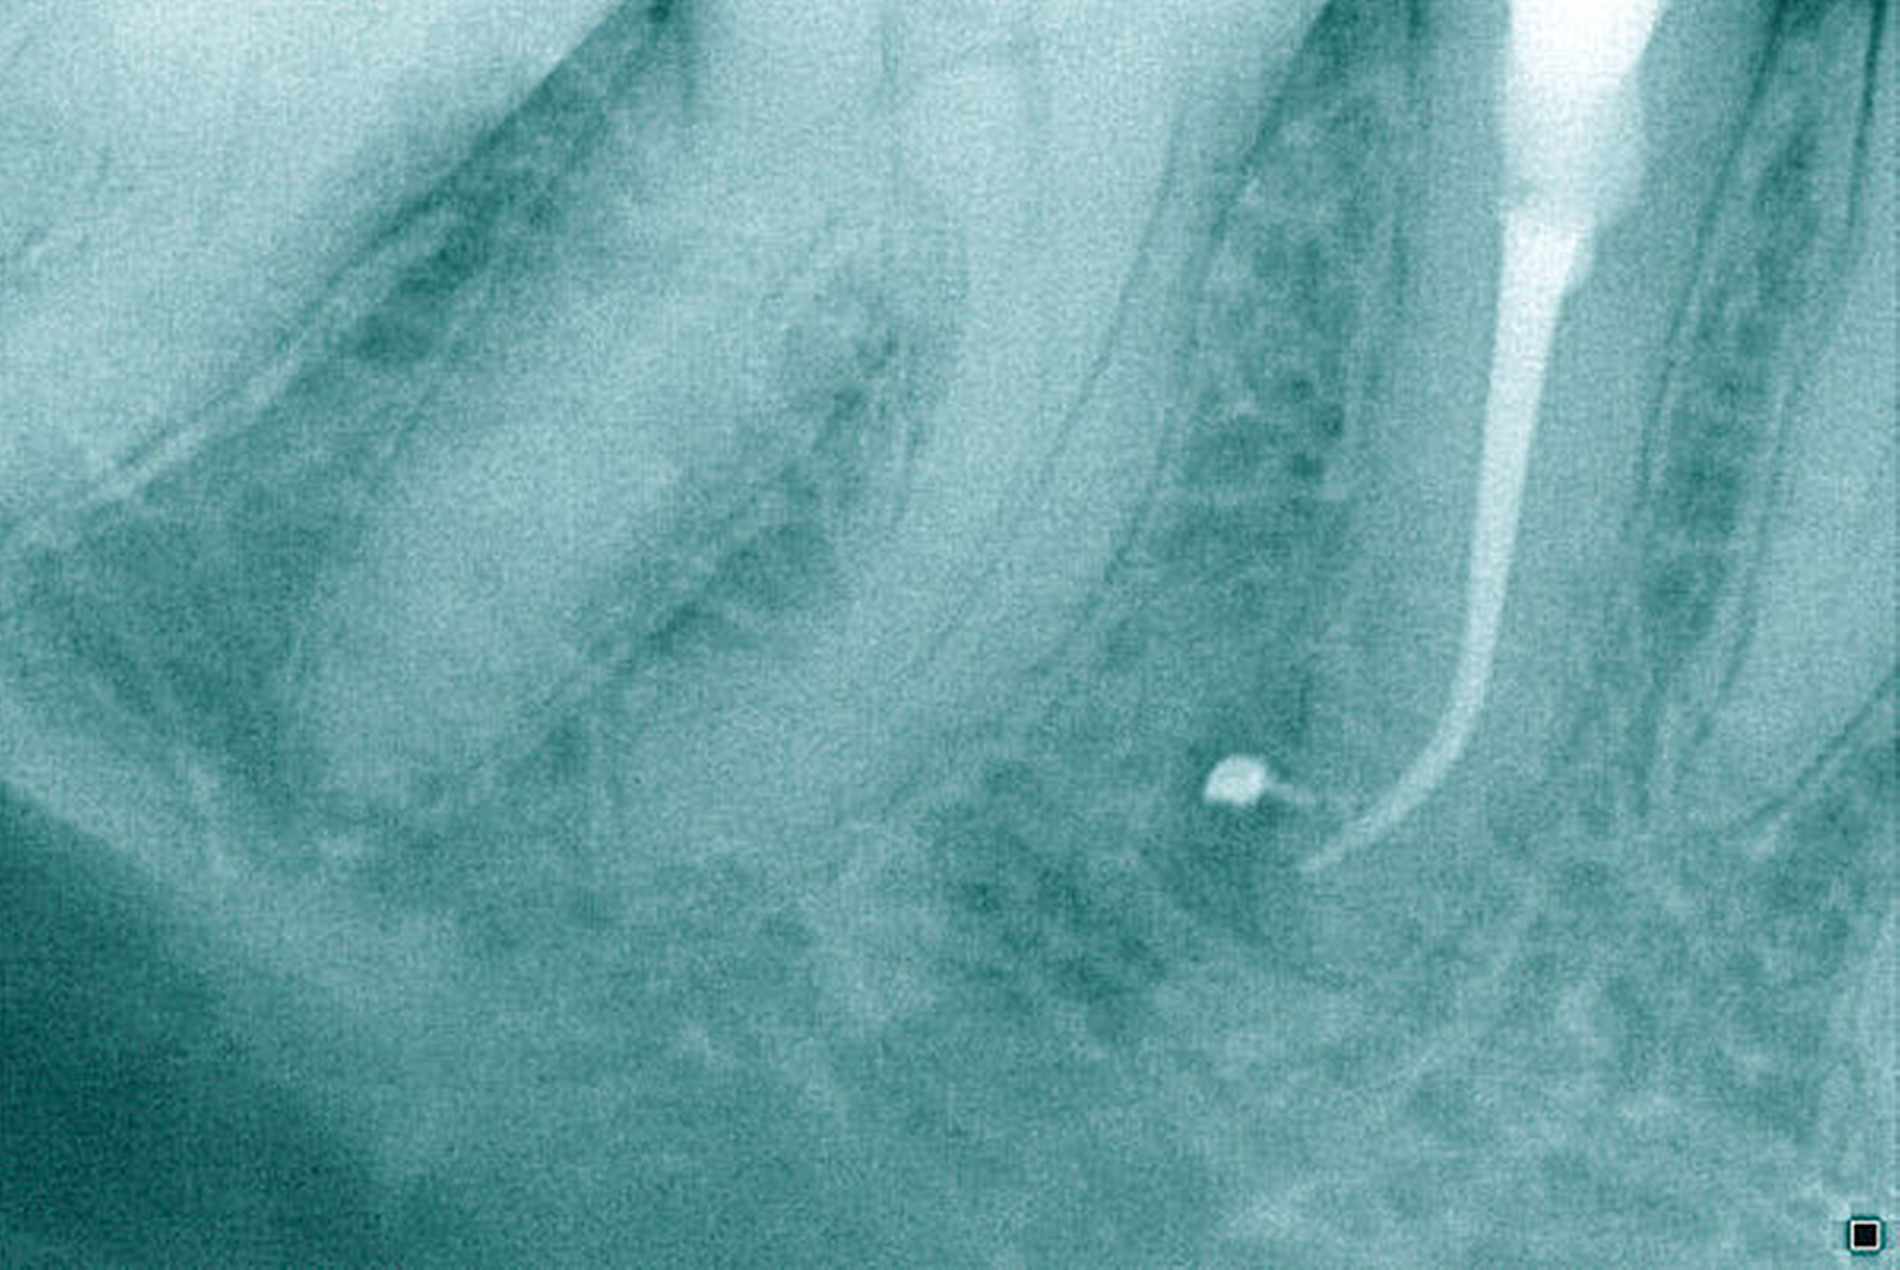

Röntgenbilder können genutzt werden, den anatomischen Schwierigkeitsgrad zu ermitteln. Lässt sich ein Wurzelkanal vollständig bis zum Apex mit einem Krümmungswinkel bis zu 30 Grad und einem großen gleichmäßigen Krümmungsradius erkennen, ist keine erhöhte Schwierigkeit in der Therapie zu erwarten (Abbildungen 1 und 2).

Krümmungsradius: Ist demgegenüber der Verlauf des Wurzelkanals unterbrochen, kann meist mit einer tiefen Wurzelkanalaufteilung gerechnet werden (Abbildung 3) [Reuver, 2002].